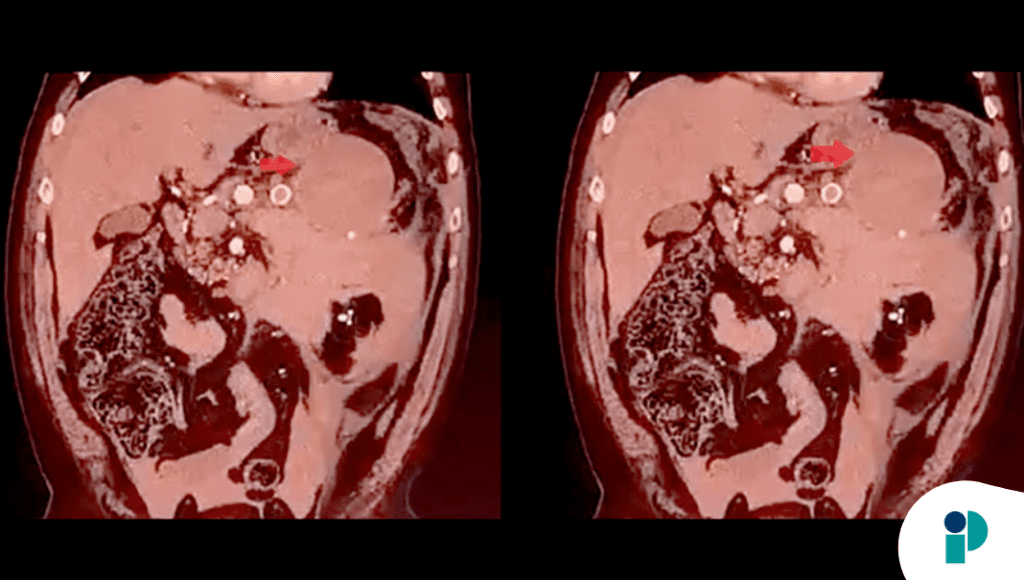

El paciente llegó al hospital con un cuadro de dolor abdominal intenso, hipotensión severa y colapso circulatorio. Las imágenes de diagnóstico inicial confirmaron lo peor: el aneurisma, una dilatación anormal en la arteria que suministra sangre al bazo, se había roto, provocando una hemorragia masiva en la cavidad abdominal.

Al realizar evaluaciones más profundas, descubrieron que el propio cuerpo había generado un trombo (coágulo) espontáneo que selló la luz del aneurisma justo después de la rotura. Este fenómeno, extremadamente inusual, actuó como un «tapón» biológico que detuvo temporalmente el sangrado y dio a los cirujanos un margen de tiempo vital.